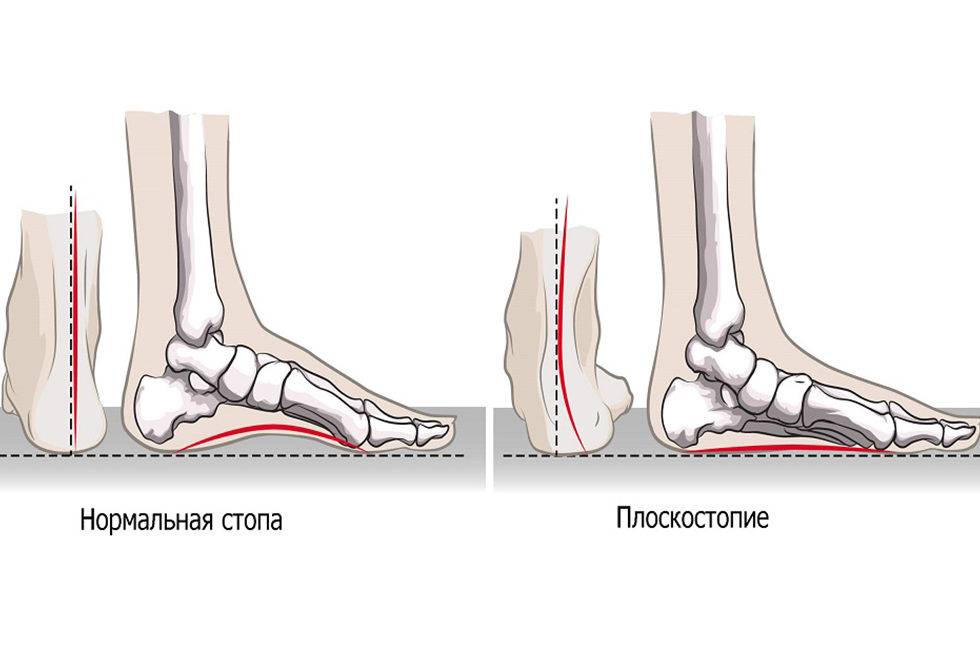

Плоскостопие

Наиболее распространенное деформационное изменение, поражающее одну либо обе стопы, проявляющееся в опускании свода, на фоне которого исчезает «арка».

Эта патология влечет за собой и другие последствия. У человека, страдающего от плоскостопия, механика коленных суставов начинает работать иным образом.

Это меняет распределение нормальной нагрузки, походка становится другой, осанка ухудшается.

Деформация стопы проявляет себя при подборе неправильной обуви как для бега, так и для обычной ходьбы. Если пара не является подходящей, то возникает оверпронация ступни, когда перпендикулярное положение оси изменяется, то есть она начинает «заваливаться» внутрь. Проявляется это состояние быстрым изнашиванием внешней части каблуков.

Левая и правая ступни чаще всего имеют различную степень проявления плоскостопия. Это создает некоторый дисбаланс при смещении оси лодыжек, что влечет за собой неравномерную деформацию скелета и перекос фигуры. Чтобы избежать такого неблагоприятного последствия, нужно носить специальную ортопедическую обувь.

Плоскостопие — одно из наиболее часто встречаемых патологических изменений механики скелета, которое обнаружено примерно у двадцати процентов жителей развитых стран. Тем, кто страдает этим недугом, и ходить, и бегать нужно только в специальной обуви либо с использованием ортопедических стелек.

Плоскостопия чаще всего бывает два, иногда три. Поперечное, продольное и их комбинация – продольно-поперечное.

Разрешено ли бегать пациентам с плоскостопием?

Плоскостопием называется уплощение свода стопы, обуславливающее нарушение естественных амортизационных функций. Мнение некоторых людей в том, что бег при плоскостопии противопоказан из-за сильной нагрузки на стопу, ошибочно. Однако при соблюдении некоторых правил эта физическая нагрузка пойдет на пользу.

При плоскостопии происходит деформация и искривление ступней. Естественный изгиб подъема утрачивается, свод стопы опускается вниз. Больные жалуются на усиливающиеся при ходьбе боли в ногах. У женщин после ношения высоких каблуков болят пятки, появляются отеки. Постепенно формируется тяжелая походка, нарушается осанка.